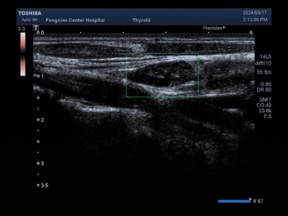

27岁的李女士就在近期体检中发现了甲状腺双侧结节,来到了奉贤区中心医院甲状腺疾病MDT门诊复查。经进一步彩超检查,发现李女士双侧甲状腺内散在细小钙化,弥漫硬化型甲状腺乳头状癌待排,TIRADS 4C类,左侧颈部Ⅳ、V、VI组淋巴结肿大伴钙化,可能为转移性淋巴结。看到检查结果的李女士惊呆了,平时不痛不痒没有任何感觉,一查竟然是癌?

为进一步精准诊断,需行甲状腺结节穿刺。但李女士的结节极小,最大仅4毫米,穿刺难度超乎想象。好在,超声医学科专家——市六医院胡兵教授专家团队成员陈磊医生与奉中心超声医学科主任陶均佳协作,精准定位,成功完成穿刺,为后续治疗奠定基础。